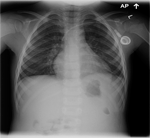

The following is a chest X-ray and CT-scan slide, showing the nice reexpansion of the left lung after few months of the surgery.

![]() Figure 13 |